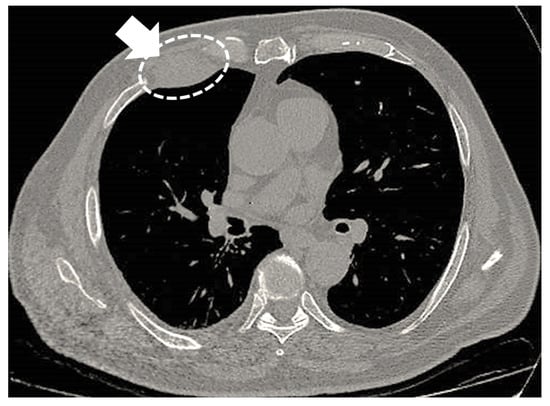

3. Unusual Radiological Presentation